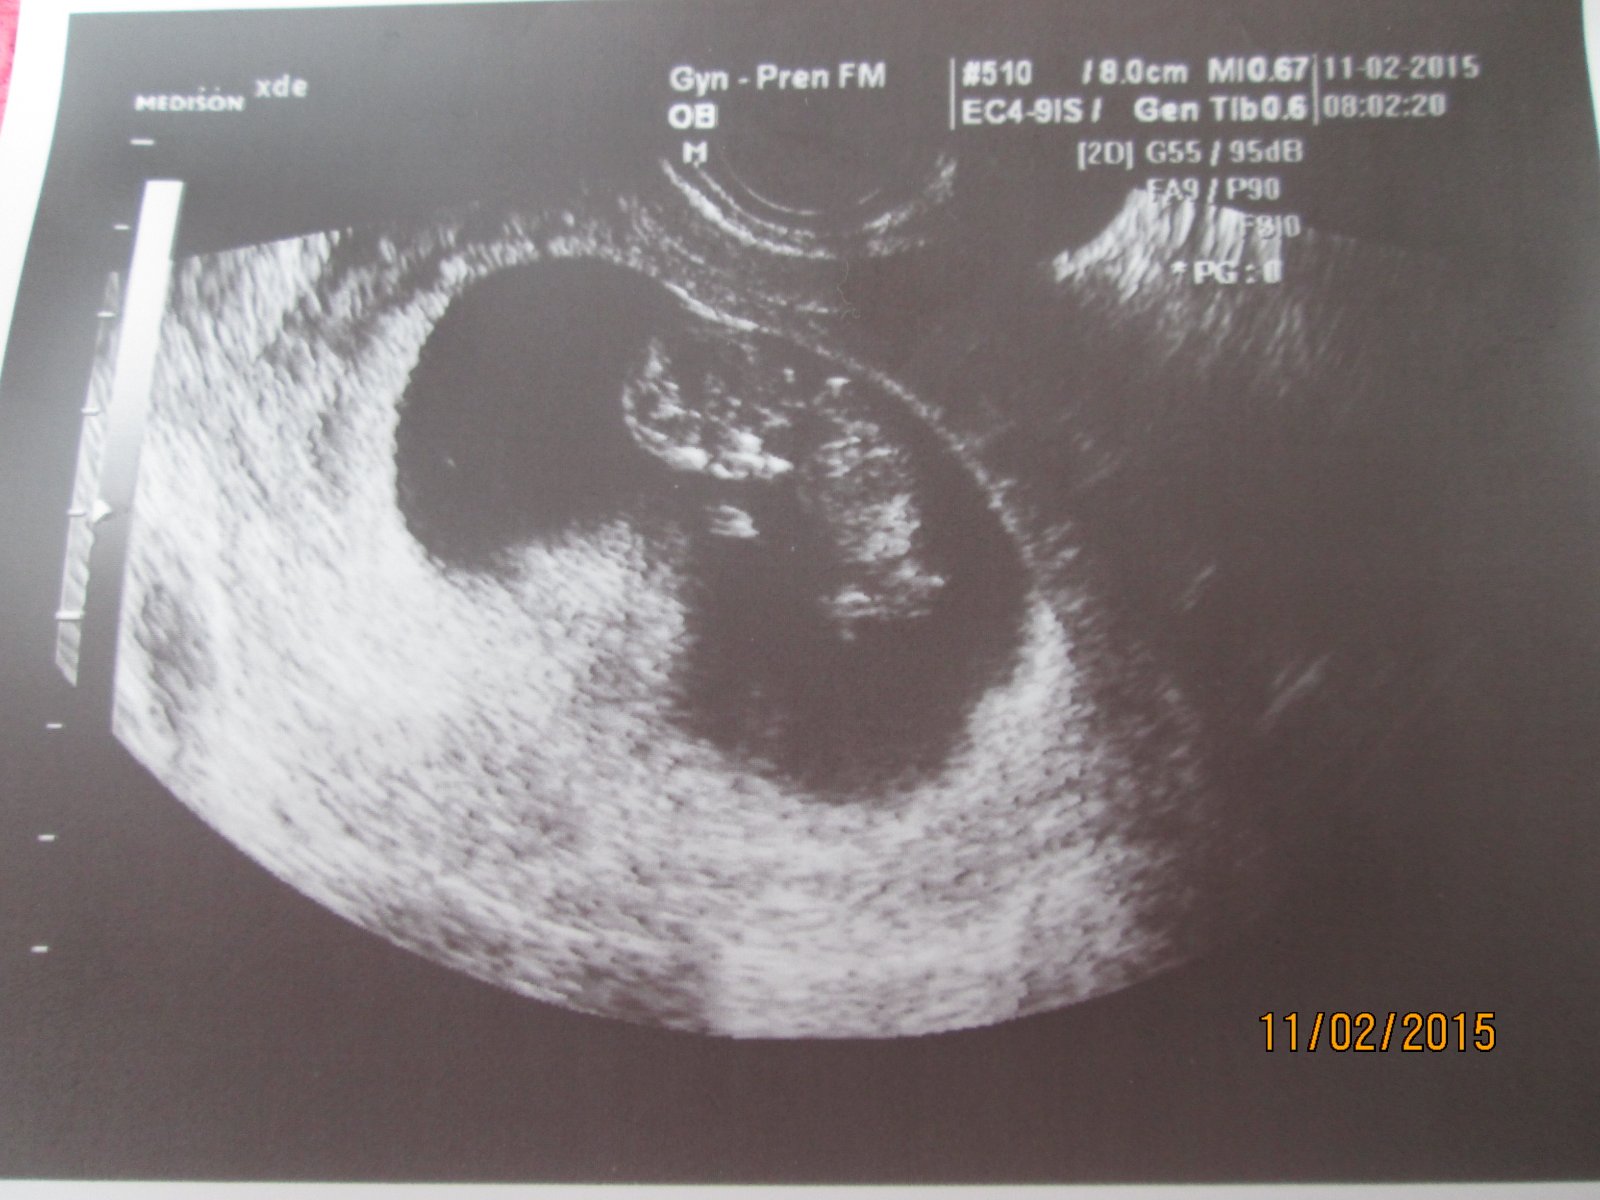

Ahojík maminečky, tak mám po kontrole 🙂 Miminko se na utz pořád hýbalo,přetáčelo,mávalo,nevydrželo ani minutku v klidu,až s smála i doktorka 😀 Brouček je naprosto v pořádku a měří 3,9 cm.Dostali jsme konečně řidičák na pupík 😀 a vzali mi 5 ampulí krve,na lačno a po cestě autem jsem to teda trošku rozdýchávala.Další kontrola 13.3 🙂 Dostali jsme i dvě fotečky,ale jelikož doktorce docházela barva v tiskárně,tak jsou trošku slabší 🙂 Na první fotečce si cumlá palec 🙂 na druhé mává tetám koníkovkám 😉